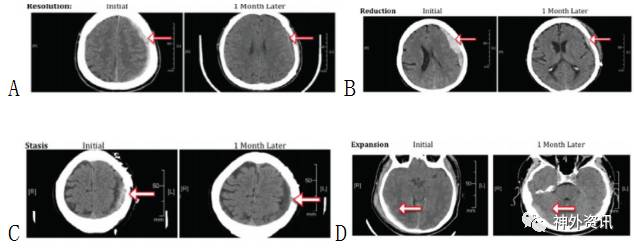

研究共纳入80例aSDH患者。作者将<65岁者归入年轻组,44例;>65岁者归为老年组,36例。从患者的年龄、性别、入院时抗凝剂和抗血小板药使用情况、手术干预或药物干预、血肿体积(图1)、凝血酶原时间、INR和临床症状等方面进行比较研究;依据入院时与1个月后血肿体积变化来评估疾病进展情况(图2)。

图2. 头颅CT扫描显示急性硬膜下血肿入院时与1月后的血肿体积改变。以入院时血肿体积为参照,A.0%–30%,消失;B.30%–65%,减少;C.65%–100%,静止;D.>100%,扩大。

研究结果提示,与年轻组相比,老年组使用抗凝剂和抗血小板药物的患者较多、女性比例大和GCS评分高。从整体来看,年轻组在入院时GCS评分较低,但恢复后的情况与老年组相仿。两组入院时血肿体积无显著差异,1个月后血肿增大或吸收和需手术治疗的状况也无显著差异(χ2 =1.514,p=0.68)。保守治疗的aSDH患者中,14.91%年轻组患者转为慢性硬膜下血肿;而老年组转为慢性硬膜下血肿占22.22%,差异无显著性。同时,抗凝剂的使用与血肿体积变化之间不存在统计学差异(χ2 =20.17,p=0.51)。两组之间凝血酶原复合物的使用情况有显著差异(Fischer检验 P<0.01);凝血酶原复合物的使用与血肿吸收呈相关性,相关系数为-0.33(95% CI:−0.571至−0.037),说明使用凝血酶原复合物可缩短康复时间。

最后作者指出,aSDH患者的疾病进展与年龄相关性不大;同时,抗凝剂的使用并不影响患者血肿的进展,而及时使用凝血酶原复合物则有助于避免血肿扩大。